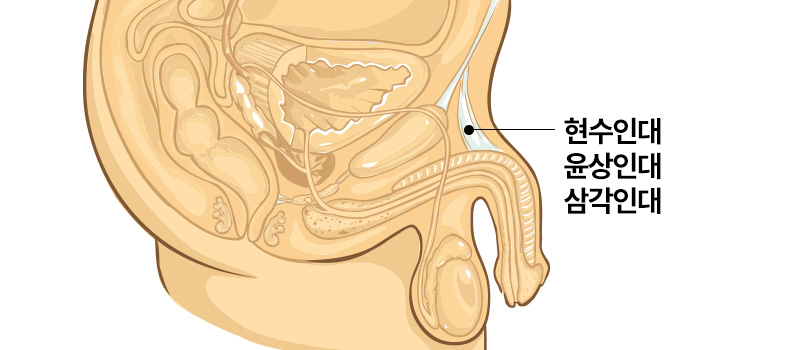

음경인대견인

성기의 인대가 과하게 발달하여

성기가 몸 안쪽으로 숨어 있는 경우

음경인대견인

강한 인대에 의해서 외부로

충분히 노출되지 못하고 있으므로

음경 근위부(성기 뿌리쪽) 인대 절제 후

발기 해면체를 이동하여 길이를 연장

*유착방지 처리로 재견인 예방